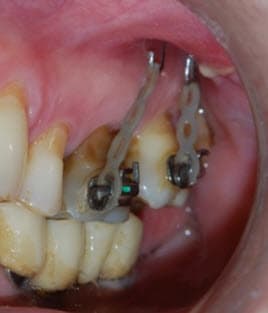

Absolument !

Pour ingresser des secondes molaires supérieures, il faut placer deux microvis en vestibulaire dans le processus zygomatique avec un CS8-1 ou un CS8-2 qui émerge en fond de vestibule, une vis transmuqueuse en palatin. On peut coller des boutons avec tractions élastiques en vestibulaire et en palatin, ou placer une chaînette élastomérique en hamac (voir les photos jointes réalisées je jour de l’intervention). On la colle alors sur la face occlusale par précaution avec une goutte de composite fluide afin qu'elle ne glisse pas. La technique chirurgicale, archi-simple est bien décrite dans le dernier article que nous avons publié (décembre 2016) et pour lequel je te mets un lien DropBox. Une simple anesthésie locale suffit et il n'y a aucun risque anatomique.

Le fait de mettre deux vis permet de déporter le crochet de suspension plus en distal pour tracter la 7.